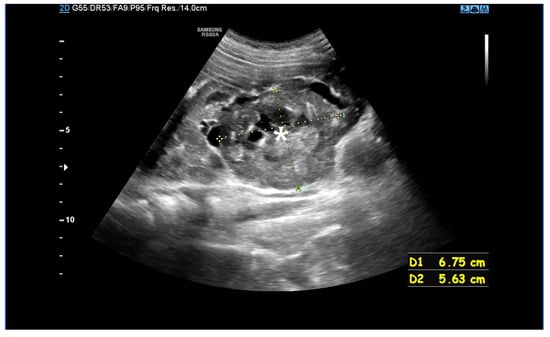

In 2–3% of patients with TSC, TSC2/PKD1 contiguous gene syndrome (CGS) is found as a distinct disease entity with clinical features typical of TSC combined with severe and early polycystic kidney disease, almost always associated with early progression to end-stage renal disease (Figure 3). The TSC2 and PKD1 genes lie in a slightly overlapping tail-tail position on the short arm of chromosome 16 (16p13.3), and the cause of the disease is a large deletion involving the 3′ end of TSC2 and extending to the neighbouring PKD1, encoding polycystin-1. There appears to be a spectrum of variability in disease severity and prognosis for CGS, reflecting allelic variation and tissue mosaicism.

Figure 3. An MRI without (A) and with a contrasting agent (B) of a 3-year-old boy with a contiguous gene deletion syndrome involving TSC2/PKD1. Both kidneys are markedly enlarged, containing numerous thin-walled cysts of varying shapes. The remaining renal parenchyma is severely deformed.